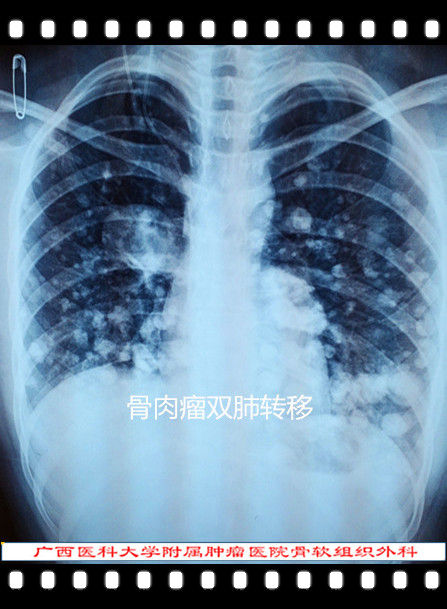

骨肉瘤的现代治疗

骨肉瘤 osteosarcoma - 知乎

骨肉瘤的影像学诊断